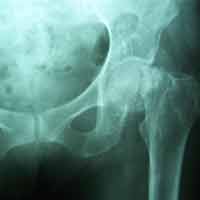

Case:11 Fracture Intracapsular Neck Femur

80 years old female patient treated with bipolar prosthesis.

Pre-Op

Post-op